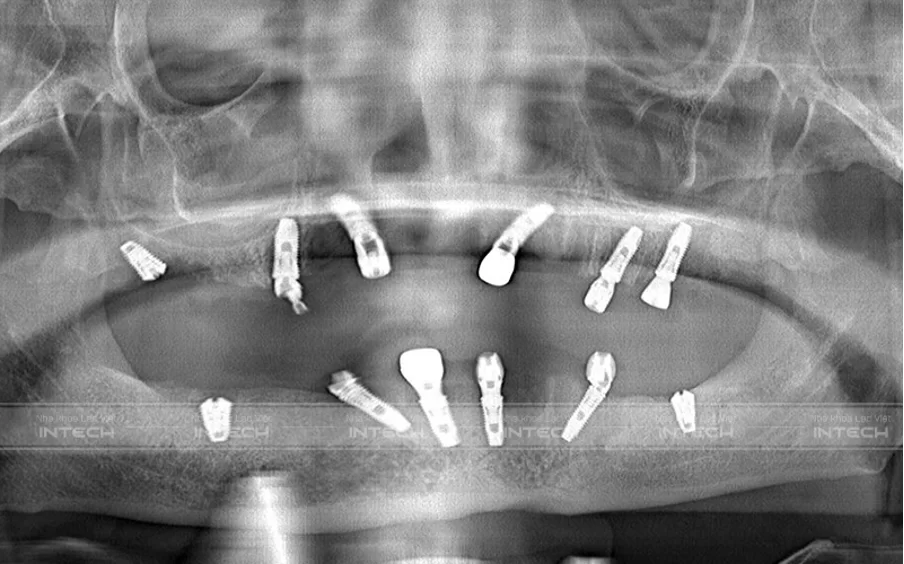

Chú Hà Hồng Bắc mất răng toàn hàm sau 25 năm do sâu răng và chăm sóc không đúng cách. Qua thăm khám và chụp phim X-quang, bác sĩ tại Nha khoa Lạc Việt Intech đánh giá tình trạng tiêu xương nghiêm trọng, thể tích xương ít cùng bệnh tiểu đường mãn tính làm ca điều trị phức tạp. Bác sĩ Hoàng Vũ Hiệp đã sử dụng phương pháp Implant toàn hàm All-On-4 kết hợp nâng xoang, ghép xương và kiểm soát bệnh tiểu đường, giúp chú Bắc lắp răng tạm chỉ sau 1 ngày và hoàn thiện răng vĩnh viễn sau 2 tháng, phục hồi chức năng ăn nhai và thẩm mỹ như răng thật.

Tình trạng mất răng toàn hai hàm, tiêu xương nặng của chú Hà Hồng Bắc trước khi điều trị